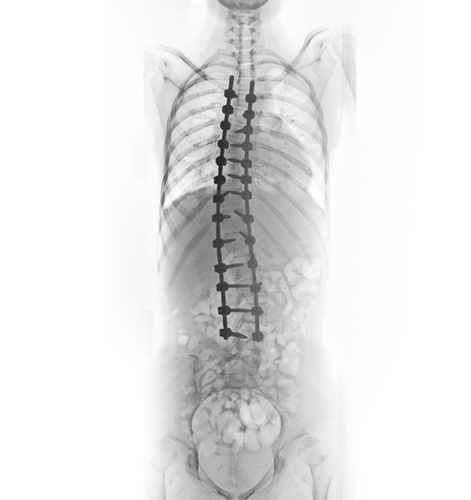

Durante a cirurgia de escoliose, o cirurgião utiliza instrumentos especializados, como parafusos, hastes e enxertos ósseos, para realinhar e estabilizar a coluna vertebral. Os parafusos são cuidadosamente inseridos em vértebras selecionadas, enquanto as hastes são conectadas aos parafusos para proporcionar suporte e correção da curvatura. Enxertos ósseos são então colocados entre as vértebras afetadas, promovendo a fusão óssea e proporcionando estabilidade adicional à coluna vertebral.